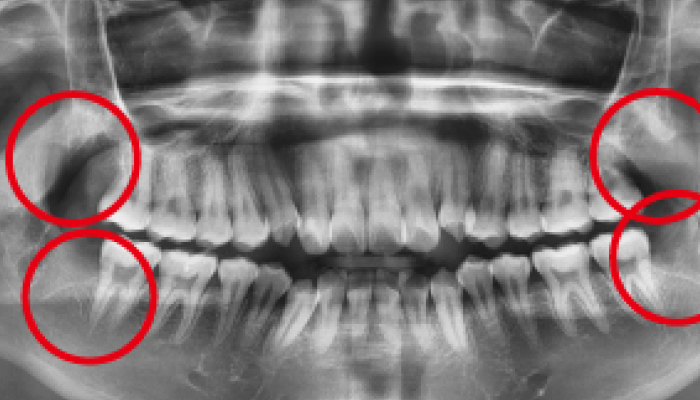

매복 사랑니 발치

이OO님 전후사진 / 치료 기간 : 30분 / 당일 사랑니 발치

매복 사랑니 발치

심OO님 전후사진 / 치료 기간 : 30분 / 당일 사랑니 발치

매복 사랑니 발치

서OO님 전후사진 / 치료 기간 : 30분 / 당일 사랑니 발치

매복 사랑니 발치

김OO님 전후사진 / 치료 기간 : 30분 / 당일 사랑니 발치

당일 사랑니 발치

이OO님 전후사진 / 치료 기간 : 30분 / 당일 사랑니 발치

매복 사랑니 발치

노OO님 전후사진 / 치료 기간 : 30분 / 당일 사랑니 발치